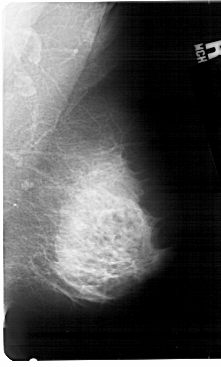

A_1396_1.RIGHT_MLO

RIGHT_MLO LINES 5491 PIXELS_PER_LINE 3301 BITS_PER_PIXEL 12 RESOLUTION 43.5 NON_OVERLAY